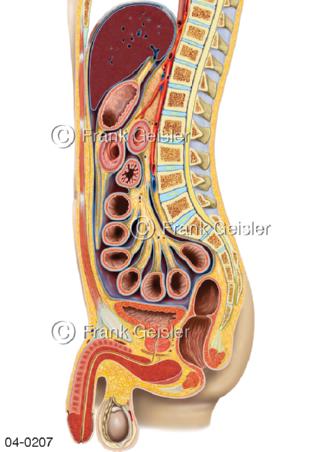

Bildergalerie Topografie Organe

Bilder zur topografischen Anatomie, die Lage der Organe und die Strukturen nach ihren räumlichen Lagebeziehungen zueinander, Übersicht der inneren Organe im Kopf und im Rumpf, Topografie der Organe im Brustraum (Thorax) und im Bauchraum (Abdomen)